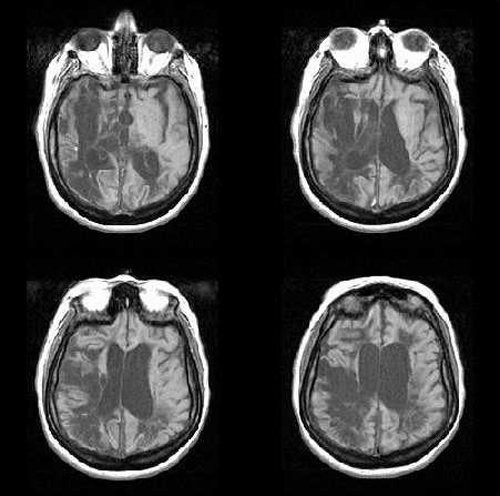

Alcuni scienziati provenienti da Belgio, Brasile, Francia e Portogallo, sotto la direzione del neuroscienziato cognitivo Stanislas Dehaene dell’Institut National de la Santé et de la Recherche Médicale (INSERM) di Gif-sur-Yvette, in Francia, si sono posti l’obiettivo di scoprire se l’alfabetizzazione migliora le funzioni cerebrali e se comporta, eventualmente, delle perdite. Gli studiosi hanno misurato le risposte cerebrali di 63 soggetti portoghesi e brasiliani alla lingua scritta e parlata, a immagini di volti, case e diversi utensili utilizzando la risonanza magnetica funzionale (magnetic resonance imaging, MRI). Nel complesso 10 volontari erano analfabeti, 22 erano stati alfabetizzati in età adulta e 31 avevano imparato a leggere durante l’infanzia.

I risultati hanno mostrato che tutti manifestavano reazioni più incisive alla parola scritta in diverse regioni del cervello, preposte ad elaborare ciò che vediamo. Inoltre, nei soggetti alfabetizzati (ma non in quelli analfabeti) le parole scritte hanno innescato l’attività cerebrale nelle regioni del lobo temporale sinistro che reagiscono alla lingua parlata. Secondo l’équipe, questo suggerisce che la lettura usa circuiti neurali che si sono evoluti per supportare la lingua parlata, una forma della comunicazione umana molto più antica della lettura. La lettura, infatti, è un fenomeno relativamente recente nella storia umana (5000 anni circa).

“L’alfabetizzazione, che sia acquisita durante l’infanzia o in età adulta, migliora le risposte cerebrali almeno in tre modi diversi”, hanno scritto gli autori nel loro documento. Essi hanno spiegato che “promuove l’organizzazione delle cortecce visive”, la porzione del cervello che riceve ed elabora gli impulsi dei nervi ottici. L’alfabetizzazione produce questo effetto “soprattutto inducendo una reazione ottimizzata alla grafia nota nell’area della forma visiva delle parole (VWFA, visual word form area) nella corteccia occipito-temporale sinistra e aumentando le risposte visive precoci nella corteccia occipitale, in maniera parzialmente retinotopica”, hanno evidenziato gli studiosi.

In secondo luogo – secondo l’équipe – “l’alfabetizzazione fa sì che praticamente tutta la rete della lingua parlata nell’emisfero sinistro sia attivata dalle frasi scritte. In questo modo, la lettura, una ‘scoperta’ culturale tardiva, influenza l’efficienza di uno dei più evoluti canali di comunicazione umani: la parola”.

Infine, gli scienziati hanno scritto che la loro ricerca prova che “l’alfabetizzazione affina l’elaborazione della lingua parlata migliorando una regione fonologica, il planum temporale, e rendendo disponibile un codice ortografico con una modalità dall’alto verso il basso (top-down)”.

Tuttavia, tutta questa attività cerebrale supplementare potrebbe avere degli svantaggi. I ricercatori hanno scoperto che nelle persone che avevano imparato a leggere in età precoce era più piccola la regione della corteccia occipito-temporale che rispondeva alle immagini di volti di quanto non fosse nei volontari analfabeti.